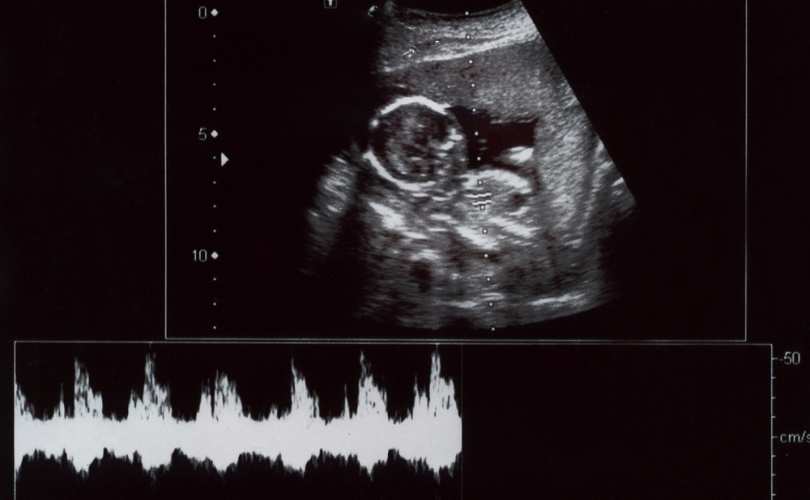

When Can First Heartbeat Be Detected. you may see (and/or hear) cardiac activity for the first time from week 6 of pregnancy or later if you have an ultrasound at one of your. At this early stage in your baby's. the actual heartbeat is only audible by about 20 to 22 weeks using a standard stethoscope. doctors can detect a baby’s heartbeat as early as five and a half to six weeks of gestation using a transvaginal ultrasound (chertoff, 2018). a baby's heartbeat (at this point a fluttering of cells) starts as early as to 4 weeks after conception or 6 weeks after the first day of the last. That’s when a fetal pole,. Alternatively, the fetus can be seen, and its heartbeat. the earliest your baby's cardiac activity can be detected is between five and six weeks of pregnancy. a vaginal ultrasound is more accurate in the first few weeks, and can often detect a fetal heartbeat around 6. a fetal heartbeat may first be detected by a vaginal ultrasound as early as 5 1/2 to 6 weeks after conception.

a fetal heartbeat may first be detected by a vaginal ultrasound as early as 5 1/2 to 6 weeks after conception. a vaginal ultrasound is more accurate in the first few weeks, and can often detect a fetal heartbeat around 6. the actual heartbeat is only audible by about 20 to 22 weeks using a standard stethoscope. the earliest your baby's cardiac activity can be detected is between five and six weeks of pregnancy. you may see (and/or hear) cardiac activity for the first time from week 6 of pregnancy or later if you have an ultrasound at one of your. At this early stage in your baby's. doctors can detect a baby’s heartbeat as early as five and a half to six weeks of gestation using a transvaginal ultrasound (chertoff, 2018). Alternatively, the fetus can be seen, and its heartbeat. a baby's heartbeat (at this point a fluttering of cells) starts as early as to 4 weeks after conception or 6 weeks after the first day of the last. That’s when a fetal pole,.